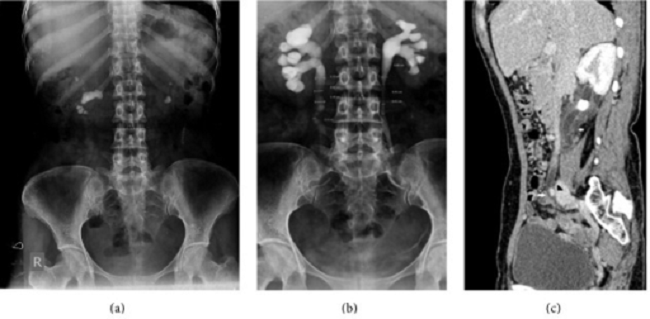

pyelografi, pyelografi intravena, pencitraan, pencitraan ginjal, urografi intravena, alomedika Sumber: Openi, 2015

Gambar 1. Intravenous Pyelography pada Urolithiasis